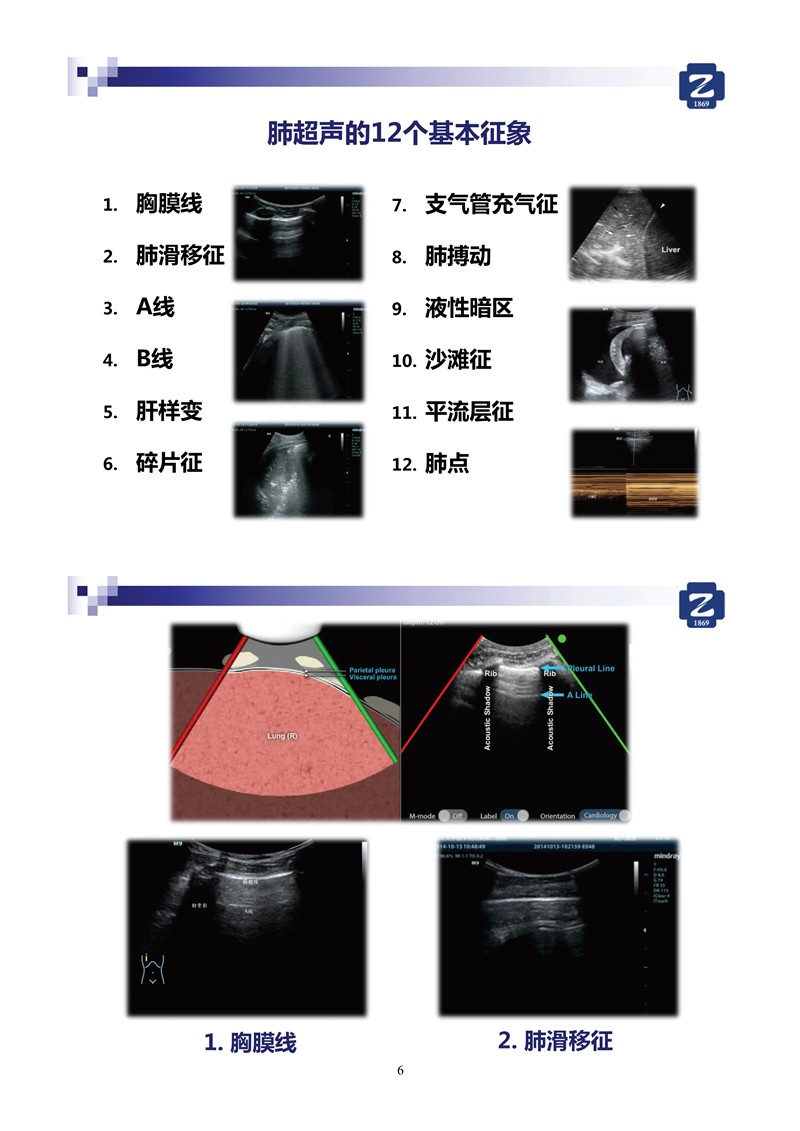

第二版新型冠狀病毒肺炎超聲診斷實用手冊(全文)